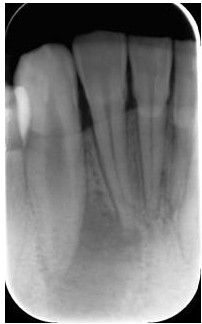

一、术前拍摄X线片评估牙齿冠、根情况以及牙槽骨情况

在根管治疗过程中,在根管治疗术前拍X线片,以帮助诊断,了解髓室的位置和根管数目及形态,测量根管工作长度及日后随访和评价疗效提供对比的依据。

拍摄X线片